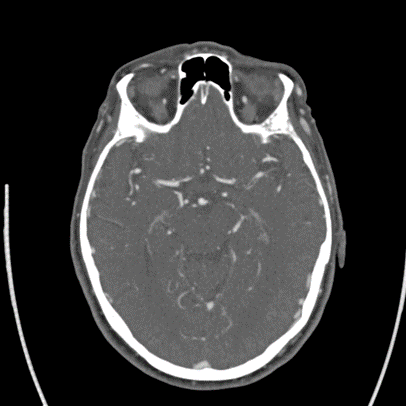

2/ Elderly person with #HTN #HLD ๐Ÿšฌ who wakes up with R-sided weakness, mild aphasia, NIHSS 8 at outside ๐Ÿฅ. ๐Ÿšซ lytics as wake-up, but CT with #denseMCA and CTA with a left M1 non occlusive thrombus. Transferred for #thrombectomy evaluation. Imaging as follows:

3/ On arrival, NIHSS now 3 for R drift, ๐Ÿ˜•, no aphasia. #CTP as below. CT still with #ASPECTS 9: